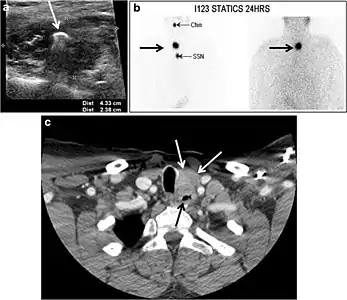

Thyroid scanning with technetium-99 m (Tc99m) plays an important role in detecting orthotopic and ectopic thyroid tissue. Both CT scans and US can help detect ectopic tissue when a lesion demonstrates imaging and enhancement characteristics of thyroid tissue. The absence of normally sited thyroid gland in US and CT scans also supports the diagnosis. In addition, US can guide FNA for cytological confirmation of a thyroid lesion. Ectopic thyroid tissue appears as a well-circumscribed, homogeneous, highly attenuating mass relative to adjacent muscles. Normally, it enhances avidly following the administration of iodinated contrast.[1]

Ectopic thyroid tissue may be detected in the tongue near the foramen cecum (90%) and along the midline between the thyroid isthmus and posterior tongue, lateral neck, mediastinum, and oral cavity. The most frequent location is the base of the tongue (Figs. 16, 1717 and and18).18). In 70% of cases, the ectopic thyroid is the only functional thyroid tissue present in the body (Fig. 18).[1]

Ectopic thyroid tissue lateral to the orthotopic midline location is rare. The exact anatomical definition of this rare entity is debated in the literature. To avoid confusion, some authors define a lateral neck ectopic thyroid as any thyroid tissue superficial to the strap muscles with no midline continuity. The majority of lateral thyroid ectopia cases have been reported as lesions closely related to the strap muscles. There are few reported cases of ectopic lateral thyroid tissue in the submandibular region, jugulodigastric region, or within the parotid gland substance (Fig. 17).[1]